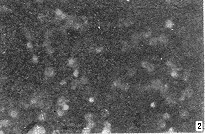

图2 CBV5感染细胞后的免疫荧光检测

Fig.2 The detection of CBV5 type antigen in Hep-2 cells infected with CBV by IFA

Showing positive fluorescence ofvirus antigen in plasma.

应用IFA、RT-PCR对CBV5接种Hep-2细胞后,对不同时间的病毒抗原和病毒RNA进行了检测,结果见表1、图1和图2。从结果可知,病毒RNA首先被检出,此后用IFA法可检测到感染细胞内的病毒抗原,光镜所见的CPE在感染后12h可见。同时,我们将CBV5接种RK-13细胞,同步观察不同时间内病毒抗原、病毒RNA、CPE均为阴性。